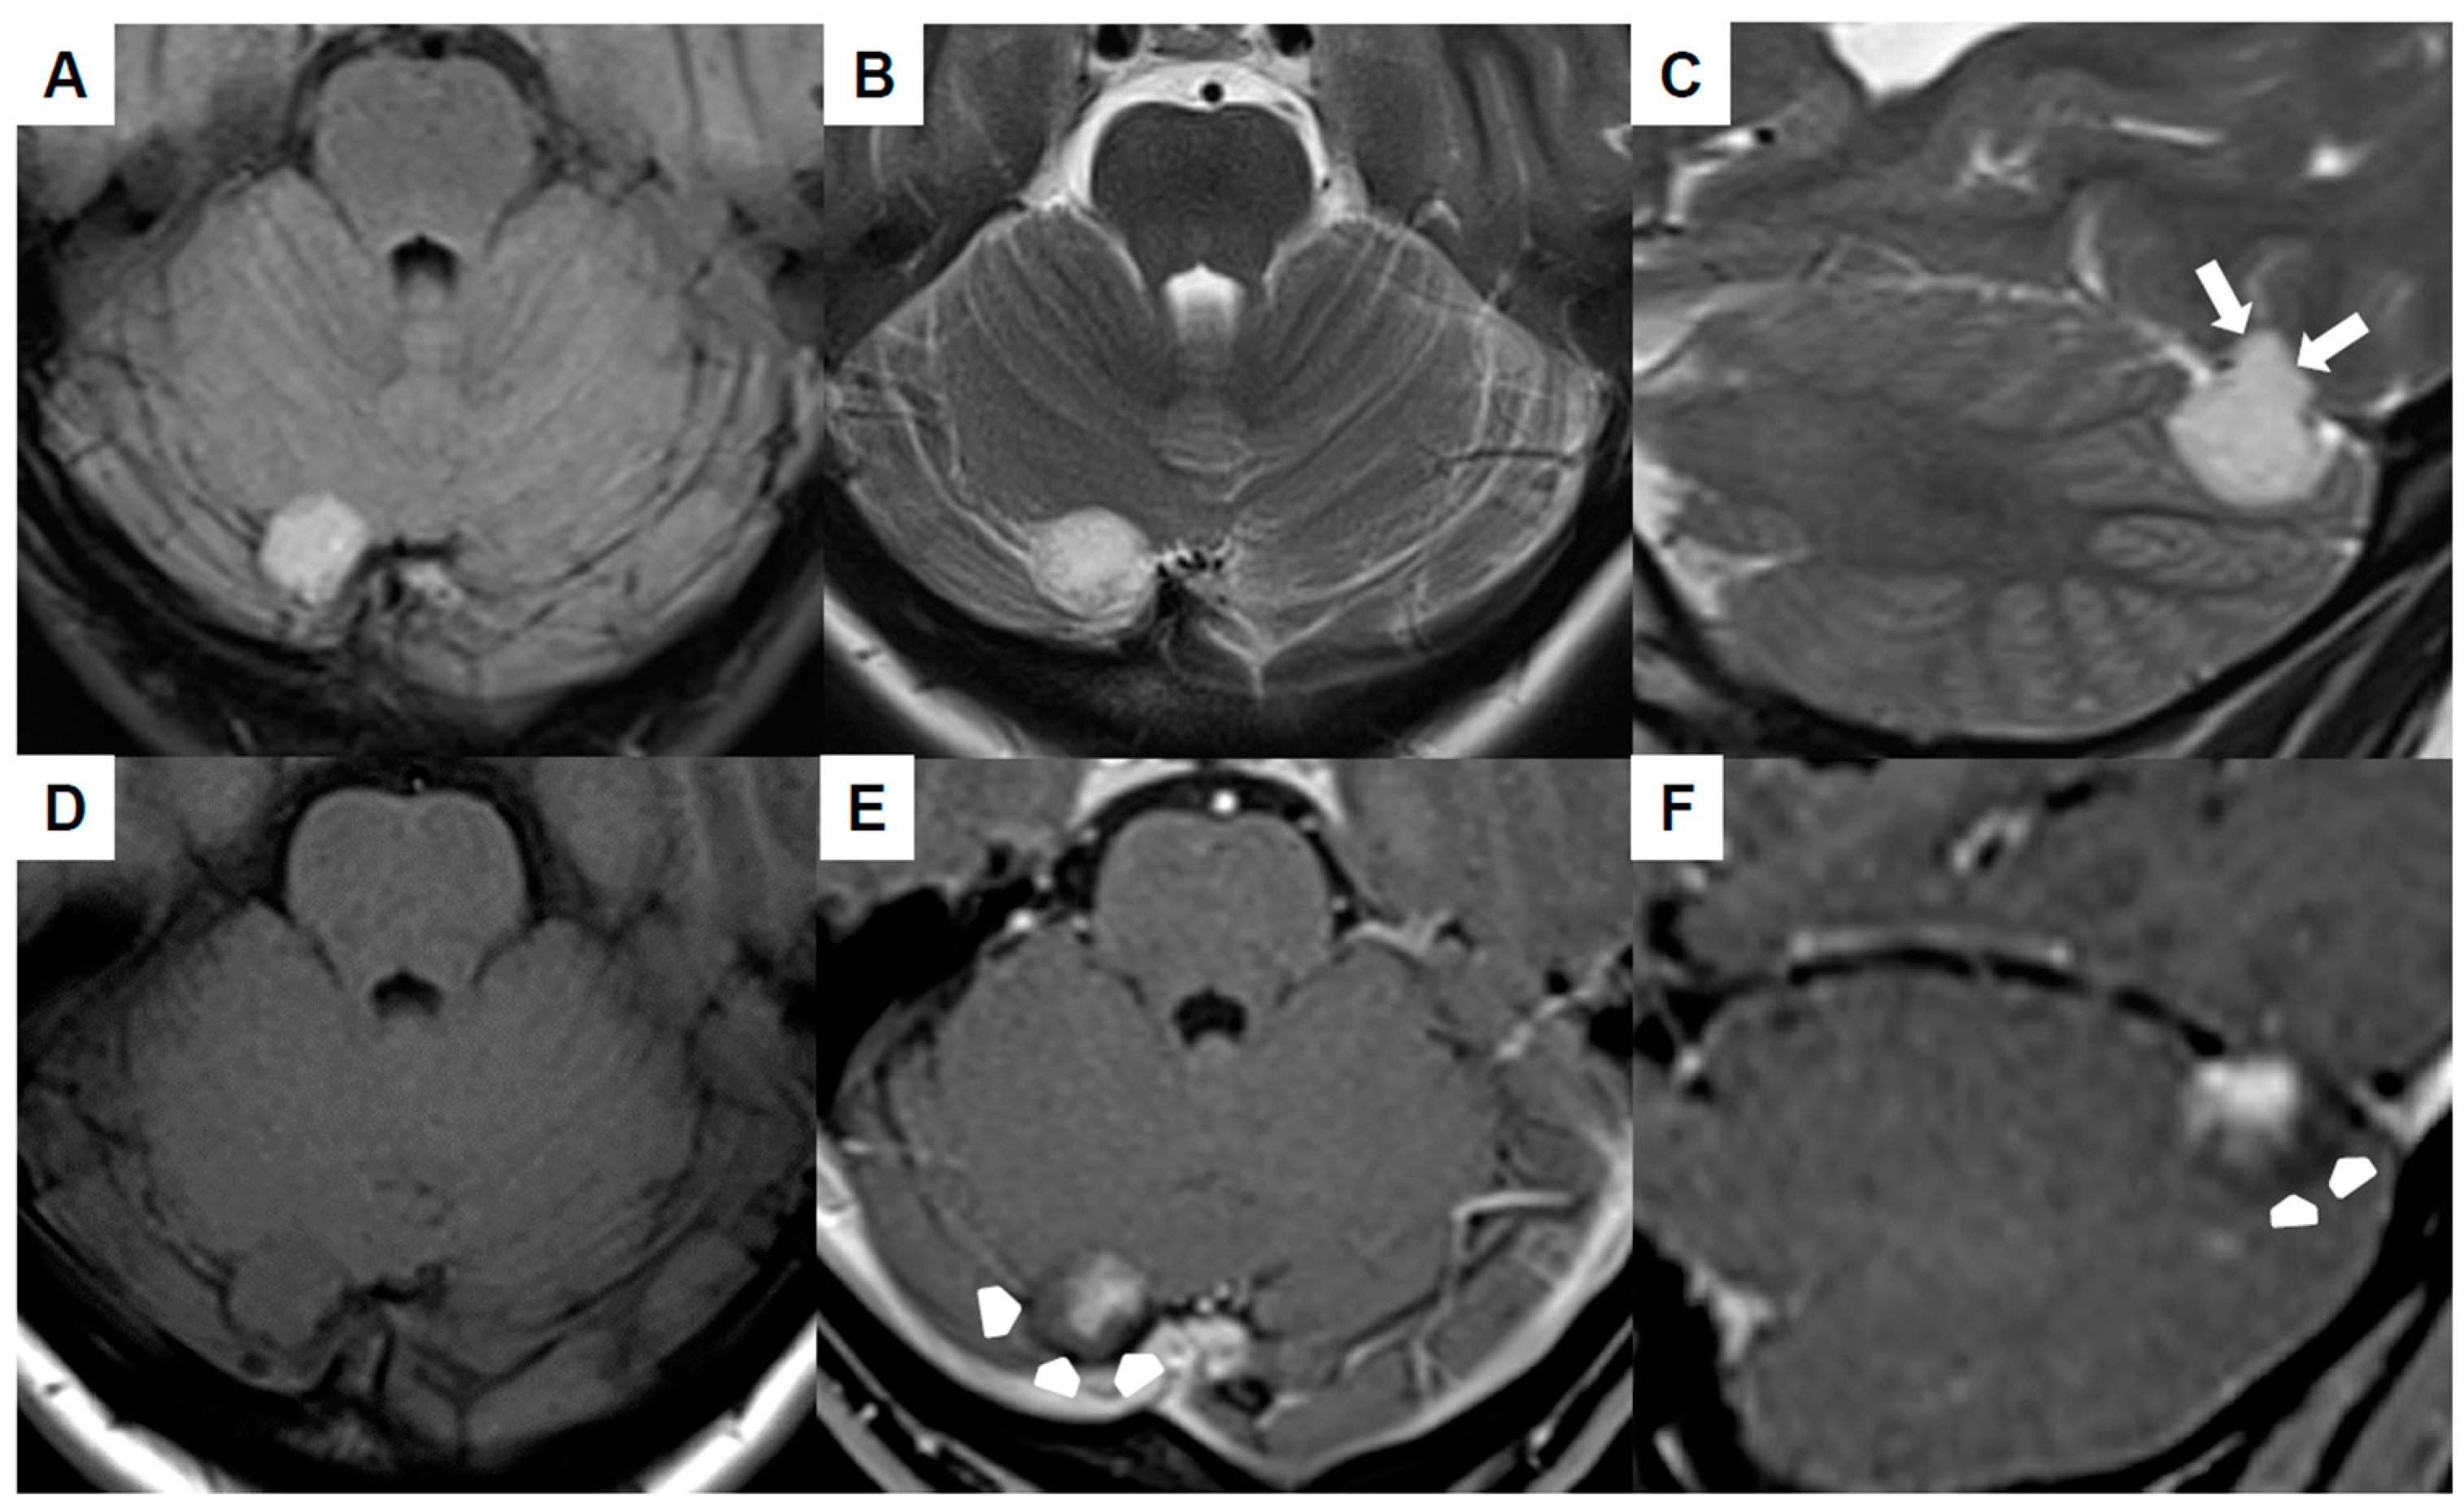

| Our first case | 34 | F | Extra-axial infratentorial on the right | Dizziness, headache, migraine (unrelated to venous hemangioma/no improvement of symptoms postoperatively) | No | 6 years | No recurrence at 3 months, No neurological deficits |

| Our second case | 52 | M | Extra-axial infratentorial on the right | Asymptomatic | No | 1.5 months | No recurrence at 5 months, No neurological deficits |